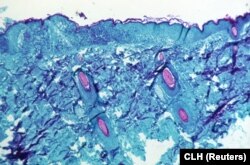

Образец ткани обезьяны, зараженной оспой